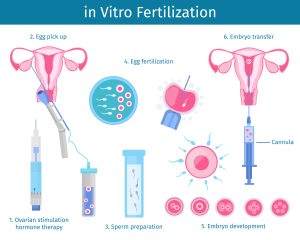

What Happens to Eggs in IVF? The Big Picture

IVF starts with a basic goal: get eggs and sperm to meet outside the body, create embryos, and transfer them back to the uterus. But how many eggs make it through this journey? To answer that, we need to zoom in on the process step-by-step. Think of it like a talent show—lots of contestants start, but only a few make it to the grand finale.

Here’s the rundown:

- Egg Retrieval: Doctors use medication to boost your ovaries into producing multiple eggs (way more than the one egg you’d naturally release each month). On average, 8-15 eggs are collected, but it varies wildly depending on age, health, and even luck.

- Fertilization: Those eggs head to the lab, where they meet the sperm. Not every egg will fertilize—some just don’t vibe with the sperm, and that’s normal.

- Embryo Development: Fertilized eggs (now embryos) grow for 3-5 days. Only the strongest survive to the point where they’re ready for transfer or freezing.

So, how many eggs fertilize? Typically, about 60-80% of retrieved eggs will successfully fertilize, but the real story is in the details. Let’s break it down further and uncover some juicy tidbits you won’t find in every article.